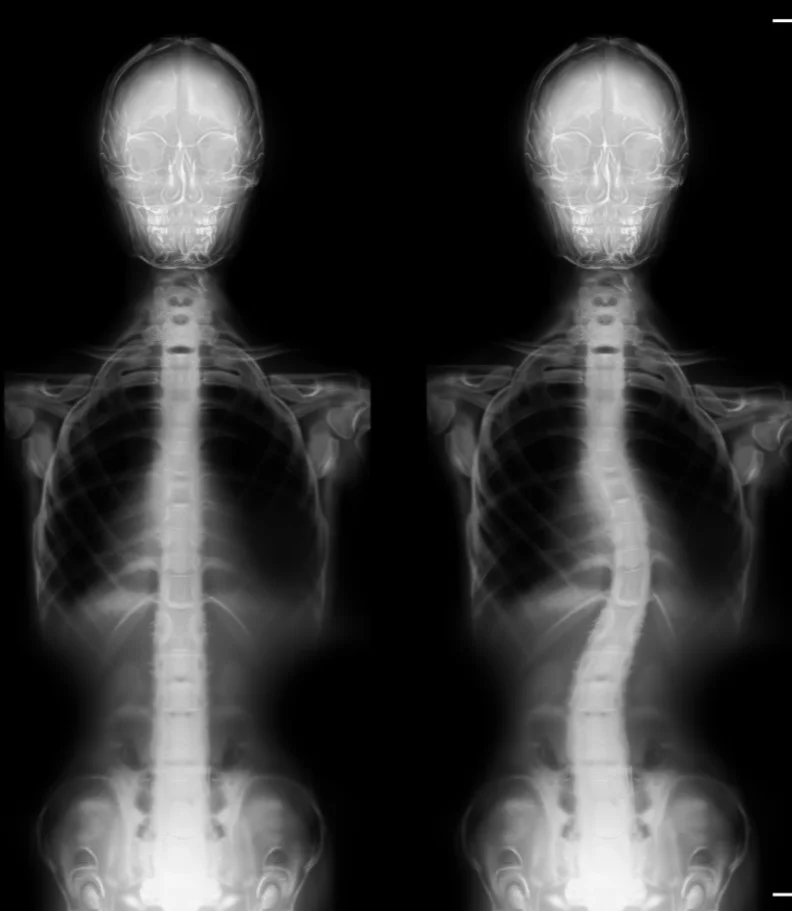

Are you in search of the finest chiropractor in Sarasota, dedicated to caring for scoliosis? Typically, scoliosis begins as a subtle curvature in the spine that gradually intensifies over time. A scoliosis diagnosis occurs when the spine deviates more than ten degrees to either the right or left when facing a medical examiner. As scoliosis advances to more severe stages, it can bring about significant health consequences.

Scoliosis manifests as an abnormal bend or curve in the spine, deviating from the ideal vertical alignment of a healthy spine. The exact origin of this curve can often be elusive. In its early stages, it may begin as a minor bend due to a single vertebra's misalignment. Over time, the body compensates by developing musculature that continues to pull the spine into lateral curves to maintain a level head position.

Often, parents or close associates are the first to notice scoliosis, as the shoulders and pelvis no longer appear level. A thorough physical examination assesses gait and utilizes visual and manual evaluations to determine the extent of spinal curvature. An Adams Position Test, involving the patient bending forward as far as possible, can reveal the presence of an issue. If a noticeable curvature is detected, an X-ray will be employed to assess the severity of scoliosis.